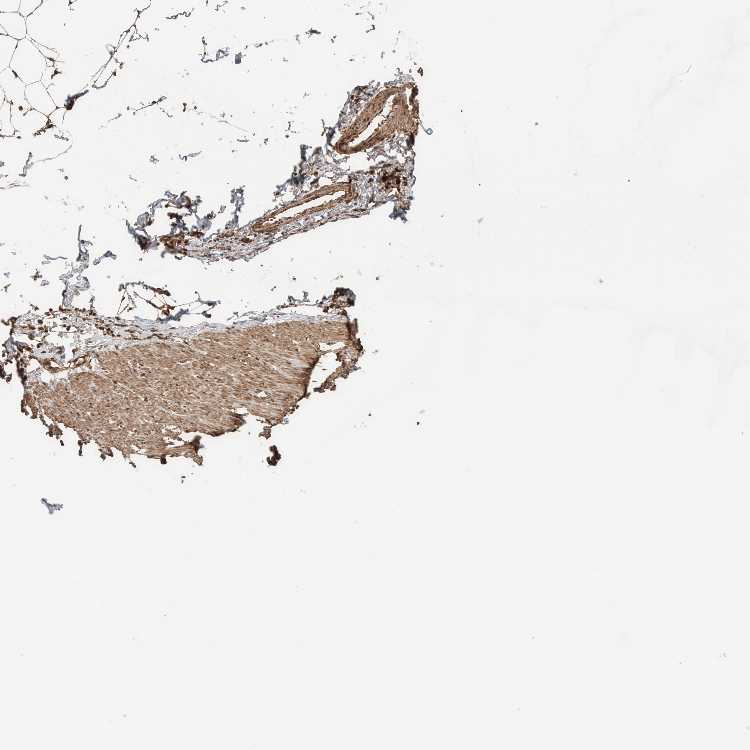

SOFT TISSUE 1 - Antibody stainingi

Antibody staining in the annotated cell types in the current human tissue is reported as not detected, low, medium, or high, based on conventional immunohistochemistry profiling in selected tissues. This score is based on the combination of the staining intensity and fraction of stained cells.

Each image is clickable and will lead to virtual microscopy that enables deeper exploration of all samples and also displays staining intensity scores, fraction scores and subcellular localization as well as patient and tissue information for each sample.

Antibody HPA023319Antibody HPA023320Antibody HPA023321Antibody HPA023325

Fibroblasts Medium-MediumMedium

Peripheral nerve HighHighMediumMedium

SOFT TISSUE 2 - Antibody stainingi

Fibroblasts HighHighHighMedium